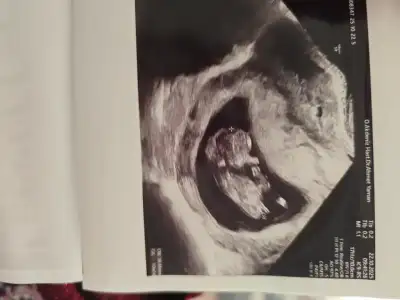

Kız bebek senesi o zaman bu sene... bizim ayın 5inde belli olacak bakalım erkek mi kız mı? Ultrason fotoğrafı yüklesem az çok tahmin eder misiniz?

Eklentiler

• 1000031246.webp

1000031246.webp

22,8 KB · Görüntüleme: 7